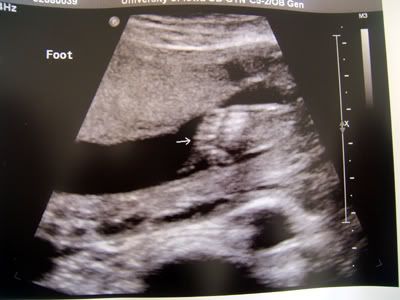

Well, as you all probably know, we're expecting an addition to our little family; a baby boy due Easter weekend this April.  We're excited!  So far, everything looks good and I'm feeling good now that the morning sickness has passed :)  Here a few u/s photos from the 20 week scan......

Foot